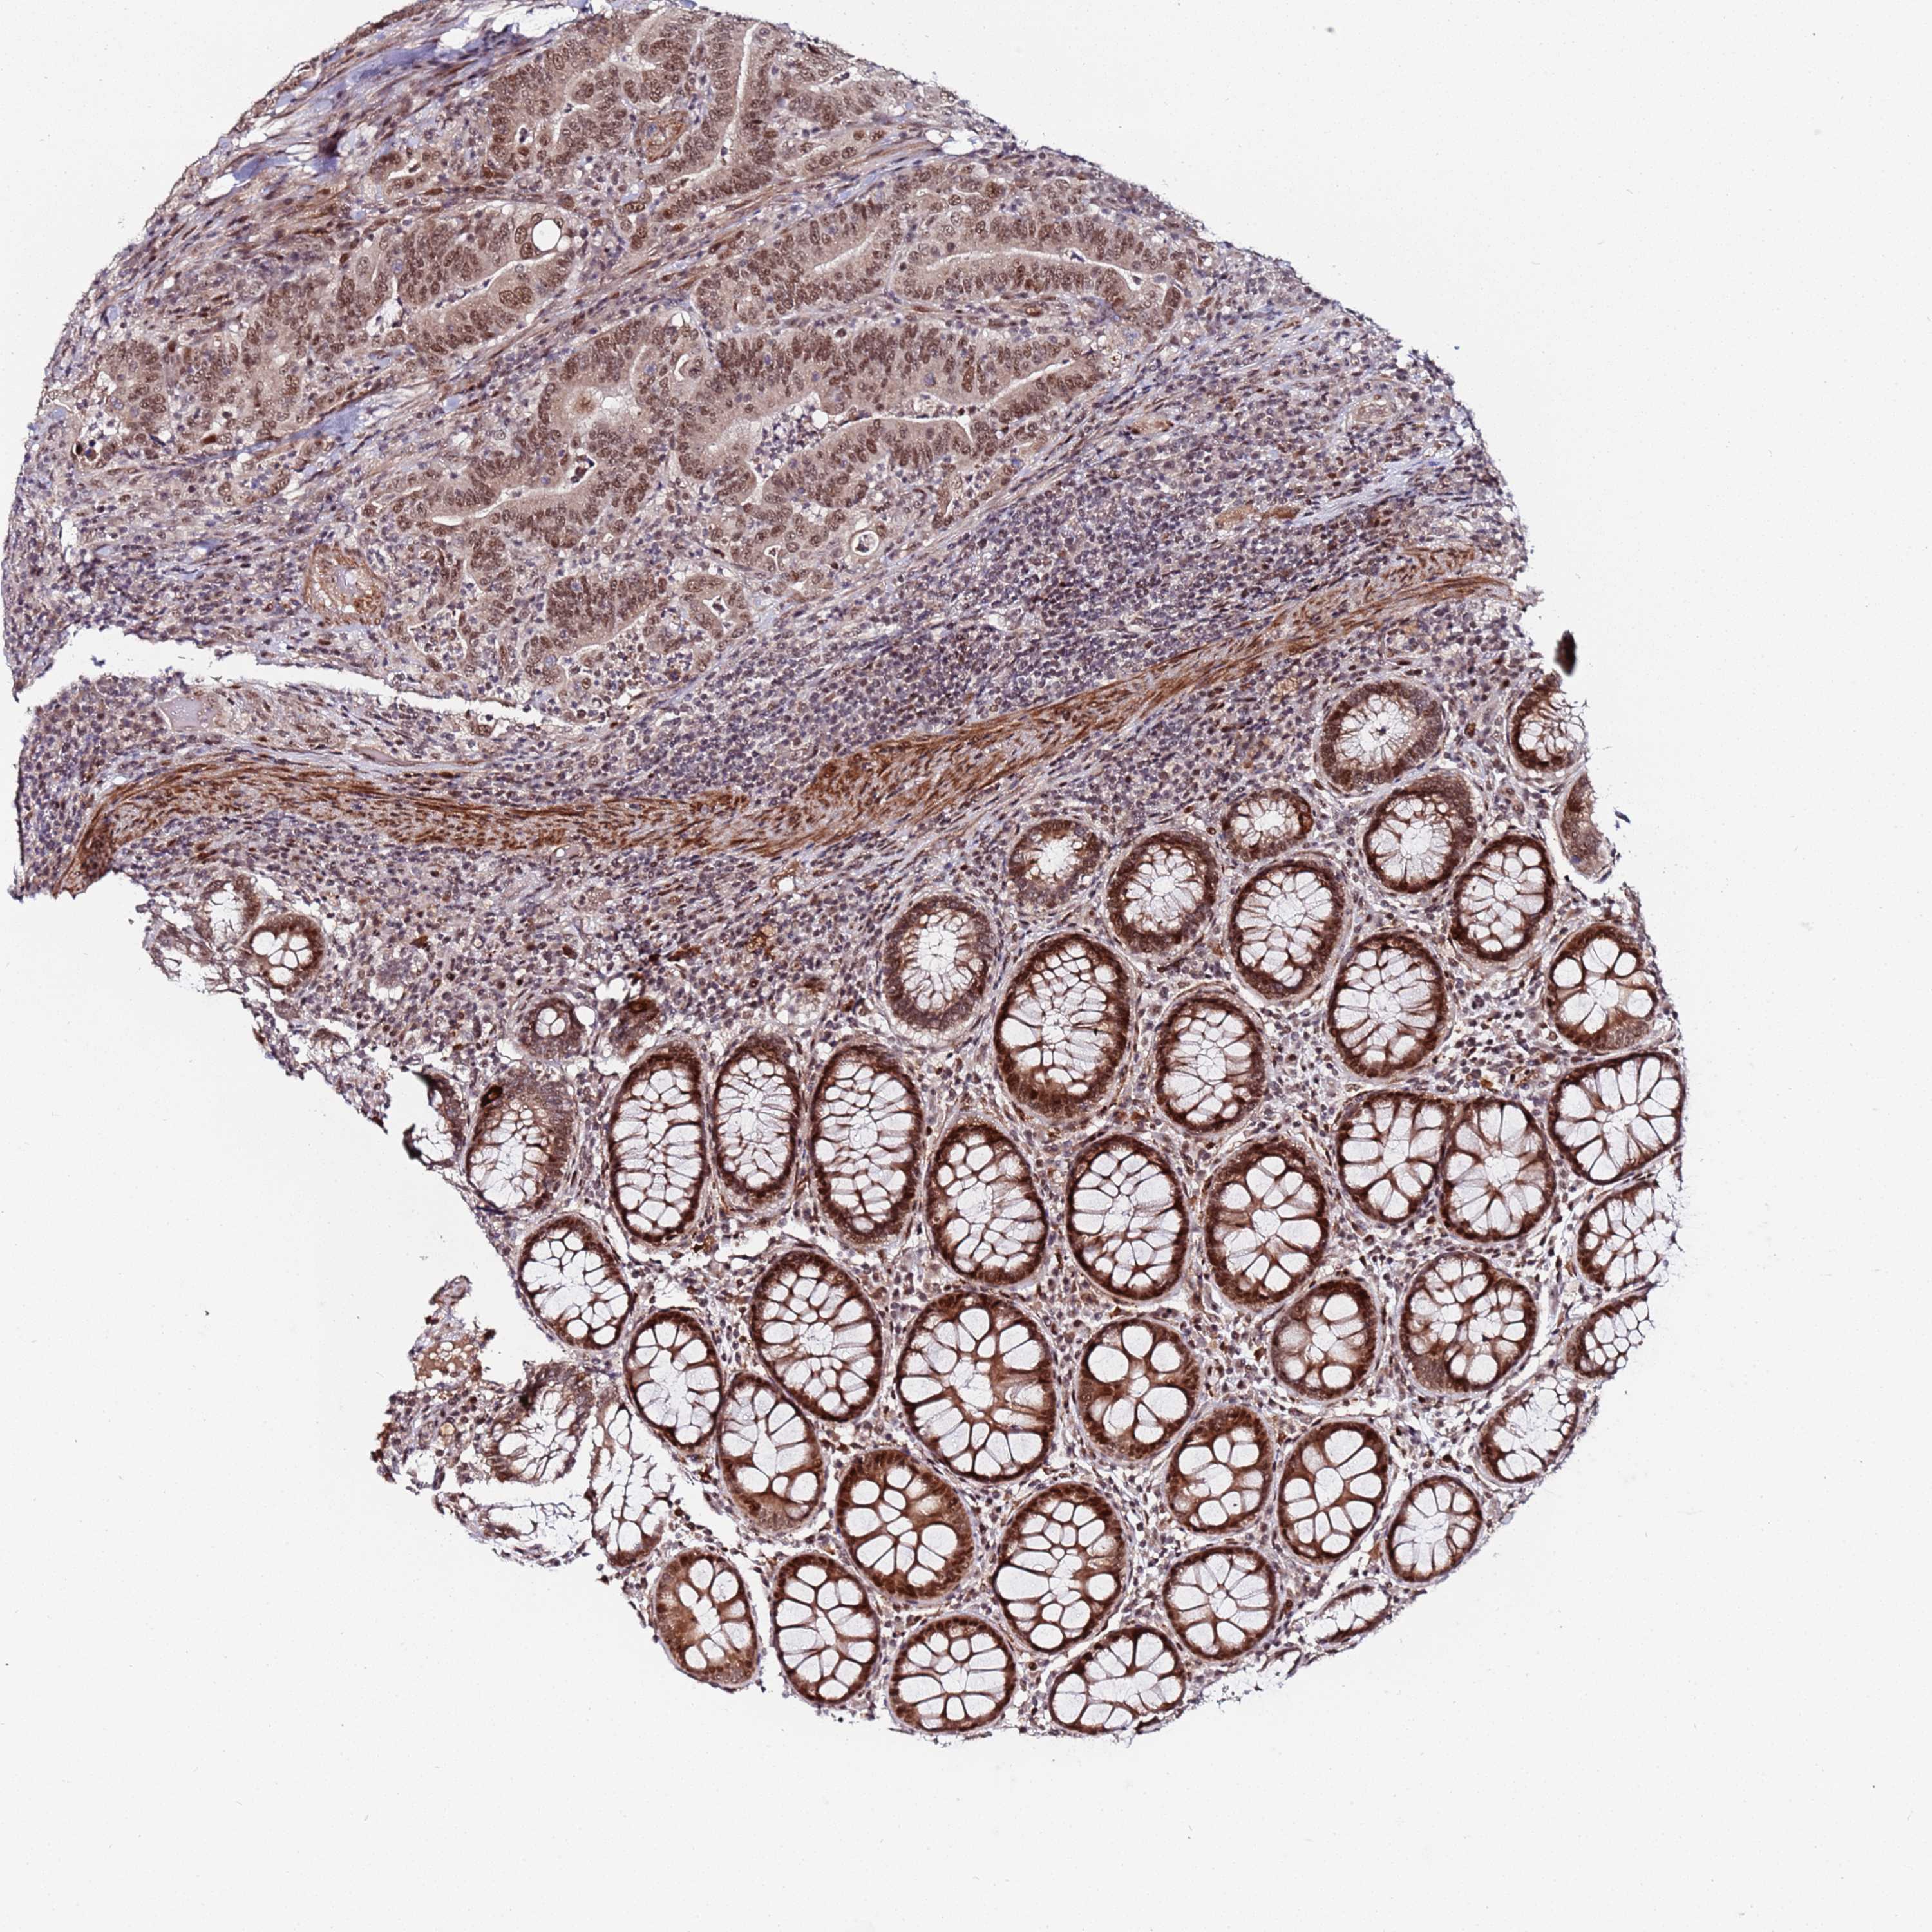

CANCER COLORECTAL CANCER Show tissue menu

Colorectal cancer

Human cancer

Colon adenocarcinoma